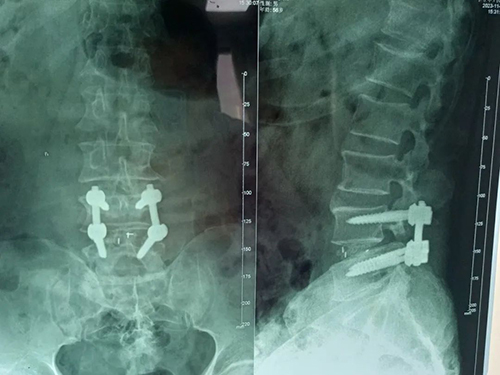

术后

我院骨科团队第一时间了解患者情况,为其安排各项检查。邹先生被确诊为:L4、5椎间盘突出症(游离型),马尾神经综合征。患者大小便功能障碍已经5天,且症状逐渐加重,情况较为紧急,于是骨科团队为邹先生在急诊全麻下行:L4/5椎间盘脱出症腰后入路+L4、L5椎体钉棒内固定+全椎板切除术+椎管扩大减压神经根松解+椎间植骨融合器融合术,手术顺利,术中成功固定L4、L5椎体钉棒,并摘除卡压神经根处的髓核组织。